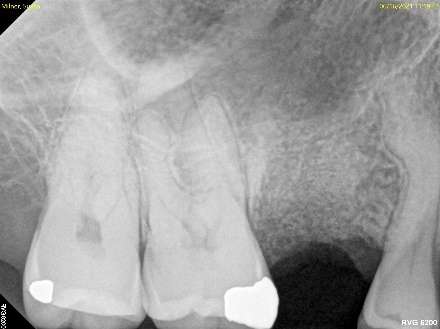

Fig. 2: Tooth Extracted, Bone Graft Placed